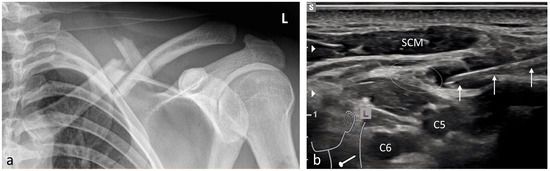

| Scapula | 8 | Brachial plexus block (interscalene)/3–5 |

| Shoulder | 99 | Brachial plexus block (interscalene)/3–5 |

| Shoulder prosthesis | 5 | Brachial plexus block (interscalene)/3–5 |

| With radiculopathy | 80 | Cervicalgia: target nerve depending on region; Lumbago: erector spinae/7–20 |